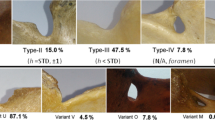

The suprascapular notches were classified according to Polguj et al. (2011). In this classification, types IV (suprascapular opening) and V (discreet notch) are recognized based on visual assessment. Types I–III were assigned based on measurements of maximal width (MW: distance between the most distant points of the upper edge of the SSN) and maximal depth of the SSN (MD: imaginary line between the level of the MW and the deepest point of the SSN) (Fig. 1). Maximal width (MW) is 0.5 mm less than the maximal depth (MD) in type I (MW < MD), equal to MD in type II (MW = MD), and 0.5 mm greater than MD in type III (MW > MD).

Among all 346 scapulae, type V (in 225 scapulae; 65.0 %) and type III (in 114 scapulae; 32.9 %) SSNs were most common. Types I and II were present in 5 (1.4 %) and 2 (0.6 %) scapulae, respectively. Figure 2 shows the representative cases of SSN types I–III.

No scapulae were found with a type IV SSN (bony foramen). The distribution of notch types according to body sides and gender is presented in Table 1. Of the 225 scapulae presenting a type V SSN, 16 cases also presented a tubercle on the superior border of the scapula, medially to the base of the coracoid process (Fig. 3).

The distribution of the SSN types differs between pediatric patients and adults. This study found type V to be present in 65.0 % of scapulae and type III in 32.9 %. In a study performed on 86 dried scapulae of adults by Polguj et al. (2011), type V was observed in 11.6 % of specimens and type III in 54.7 %. A similar study evaluating the shape of the SNN in chest CTs of adult patients found that among 619 analyzed scapulae, 55.8 % presented type III SSN and 12.9 % type V (Polguj et al. 2013a). A third study based on 762 patients from the Japanese population with a mean age of 58.2 ± 19.1 years (range 10–92 years) used three-dimensional CT to assess the shape of the SSN based on the Rengachary classification (Rengachary et al. 1979). The results indicate that 11.4 % of scapulae were classified as possessing Rengachary type I SSN, which corresponds to our type V. Although previous studies have found this type to be present in 6–21.5 % of cases, these were performed mainly on dried scapulae, and the age of the donors was unknown (Rengachary et al. 1979).

The different SSN type distribution between children and adults and the positive correlation between age and SSN size suggest that the final shape of the SSN develops with age. It should be noticed that pediatric type V SSN presented a more heterogeneous morphology than the adult type V because of the presence of the tubercle on the superior border of the scapula, which was observed in 16 cases. Hence, in children, the type V SSN should be subdivided into types Va and Vb based on the respective absence or presence of this tubercle (Fig. 2). In this sense, type Vb (“type V with tubercle”) may represent a transient form between juvenile type V of the SSN and the adult type of a different kind.

Another argument for the postnatal development of the morphology of the SSN might be the absence of type IV (the suprascapular foramen) in children. The occurrence of this type in adults ranges from 1.92 % (Inoue et al. 2014) to 7.3 % (Polguj et al. 2011). In a Polish population, it was reported in 6.2 % of specimens by cadaveric study and in 5.0 % of cases by CT examination (Polguj et al. 2012; 2013b). In the US population, its frequency is known to range between 3.7 and 5.5 % of cases (Zehetgruber et al. 2002). There is no consensus on the mechanism of its creation. The most common hypothesis assumes that the superior transverse scapular ligament may ossify with age, enclosing the osteofibrosus tunnel into a bony foramen (Inoue et al. 2014). This hypothesis is supported by observations of different degrees of STSL ossification (Polguj et al. 2011). Moreover, Inoue et al. (Inoue et al. 2014) note that patients with a bony foramen were significantly older than patients with other types of SSN. However, the same researchers also report the occurrence of a bony foramen in a 21-year-old patient. Nevertheless, our observations support the sequential development of SSN types I–IV: from type Va, through type Vb, to a final form, creating an osteofibrous tunnel together with the superior transverse scapular ligament and/or anterior coracoscapular ligament (Polguj et al. 2013b), which may further ossify.